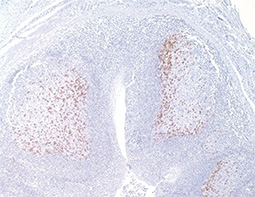

PD-L1 antibody (GTX104763) |